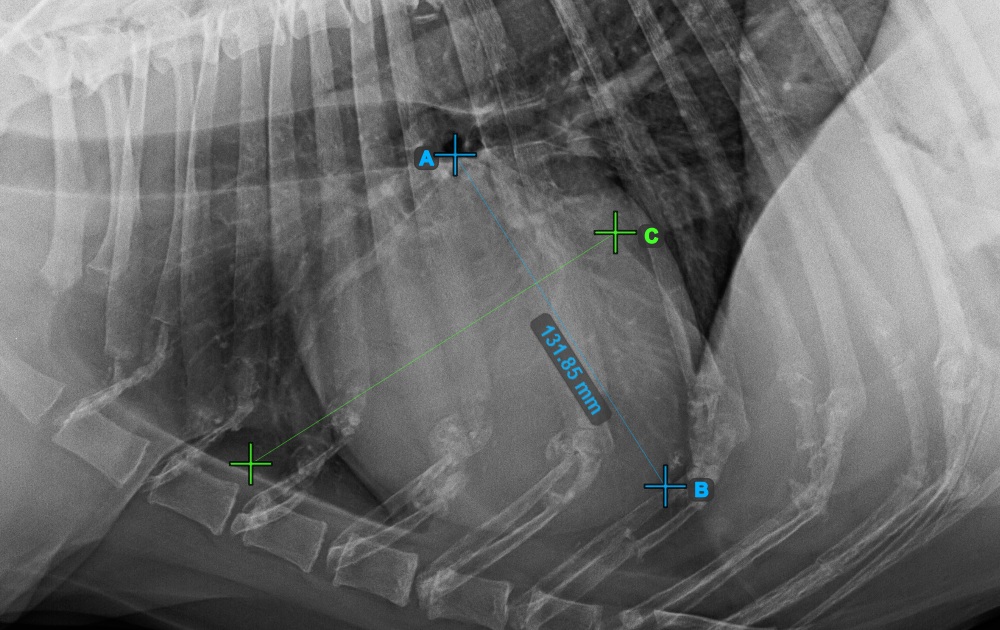

Continue the measurement by marking the widest right (cranial) point of the short axis of the heart.

The image below represents a typical placement of the most cranial point on the short axis of the heart.

Complete the short axis of the heart by marking the widest left (caudal) point.

The image below represents the typical placement of the most caudal point on the short axis of the heart.